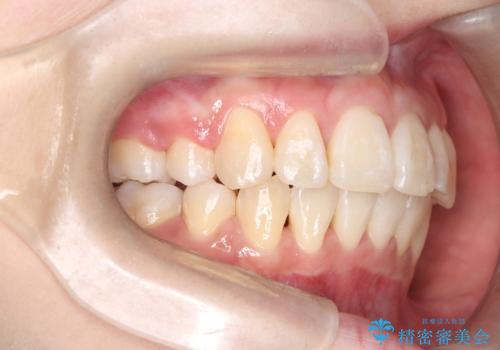

- 八重歯(叢生)と、上下の歯の中心線(正中)がずれていることを主訴にご来院されました。精密な検査の結果、歯列全体のスペースが大幅に不足しており、八重歯を正しい位置に配列し、正中のズレを改善するためには、上下左右の第一小臼歯を抜歯する必要があると診断。装置には、目立ちにくい審美ワイヤーを使用し、見た目を気にせず、機能性と審美性が完璧に整った咬み合わせを目指す治療計画を立案しました。

八重歯: 突出していた八重歯を歯列内に誘導し、デコボコを解消しました。